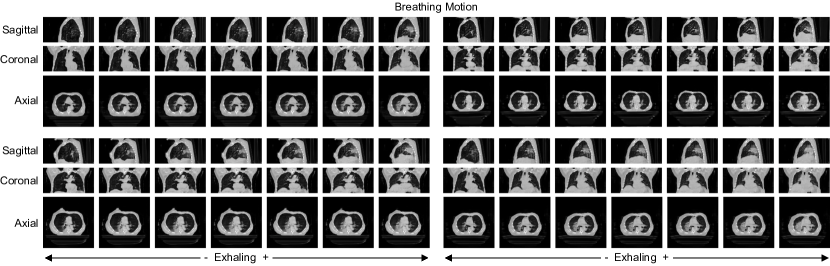

For all three datasets, we use 90%percent9090\% of the patients for training and 10%percent1010\% for testing. Figure 2 shows an example of the breathing motion and tumor regression dataset.

Refer to caption

Figure 2: Examples of breathing motion and tumor regression datasets. The presented examples are after preprocessing. For breathing motion, the center volume shows the most exhaled while the ones to the left correspond to exhaling and those to the right to inhaling. For tumor regression, we estimate the slice corresponding to the center of the tumor manually. The tumor is marked with the red bounding box.

Next, we consider the breathing motion dataset. Figure 4 presents some generated volumes for the breathing motion dataset.

Figure 4: Four examples of generated volumes with embedded shift for the proposed model on the breathing motion dataset. The center volume corresponds to the original latent vector. All images show the center slice for the sagittal, coronal, and axial view.

We observe good image quality with sufficient detail and realistic anatomy. Considering the embedding, we observe that breathing motion is captured well, and the temporal dependencies of breathing are embedded in the latent space. The clearest change when moving along the embedded direction is the diaphragm moving upward while exhaling. This is also the most obvious change observable in the real data. Additionally, we observe the stomach or rib cage contracting while exhaling. Lastly, we observe very high scene consistency. I.e., the generated scan of the patient does not change markedly while moving the latent code along the embedded direction. Thus, the patient’s anatomy is preserved, and the changes induced by moving along the embedded direction are restricted to breathing-related changes.